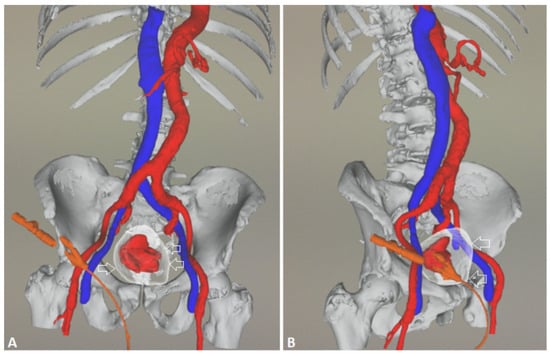

Technical Details of PAE